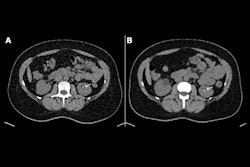

PCCT improves the iodine contrast-to-noise ratio, noted Lucie Sukupova, PhD, of the Institute for Clinical and Experimental Medicine in Prague.

"The equal weighting of photons of all energies ... [produces higher attenuation in iodine] compared to energy-integrating detector CT, which means [a] lower contrast medium dose is needed to get the same contrast-to-noise ratio as before or [a] lower radiation dose is needed to get the same contrast-to-noise ratio as before," she said.